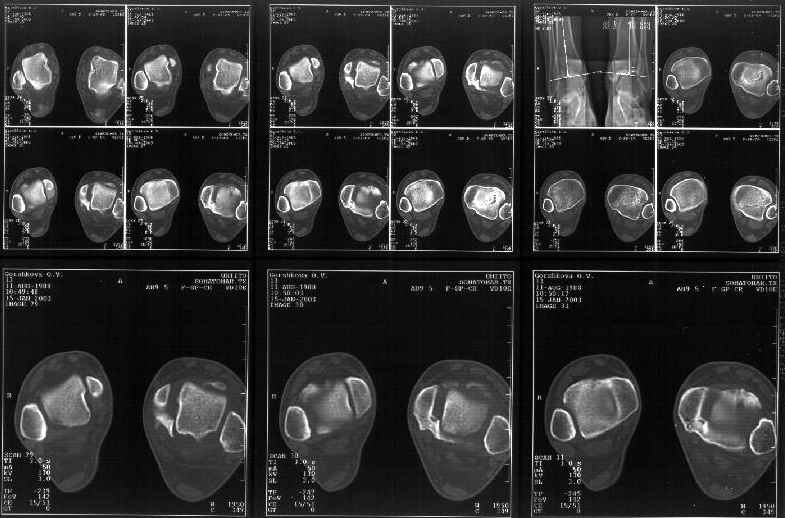

Сегодня пациентке сделали сравнительную КТ. А ксиальные и Фронтальные срезы приложены. Ваше мнение?

Фронтальные

Аксиальные

Спасибо за КТ -она изумительная. К сожалению, я по дороге на врачебный викенд на Мёртвом море и не смогу подготовить комментарий и схемку до 19.01.03 Помоему, результат КТ даёт чёткую возможность красивой и эффективной помощи.

Отправитель: Й. Воск 19 Январь 2003, 22:50

На КТ я попытался изобразить скромными своими способностями (А)- место перелома, (С)- нормальный суставной зазор меж тараном и тремя его маллеолами. (В)- образовавшийся в результате перелома широкий раза в три зазор, позволяющий, по-моему, сублюксацию тарана при ходьбе. В свете данных КТ, критически важных, я бы предложил вертикальную остеотомию места перелома

задне-внутренним подходом и фиксацию мед. маллеола прижатым к тарану с помощью тонкого compression screw. После этого гипсовый сапожок и немедленное расхаживание ноги.

Удачи, Й.Воск